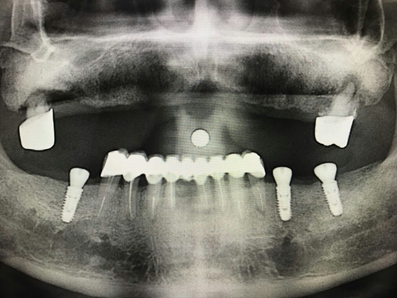

毛國(guó)斌種植病例——群討論分享